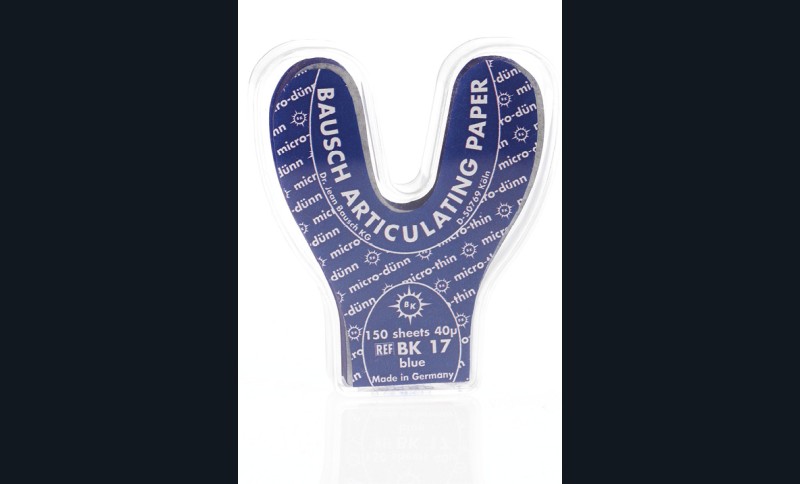

Cela permet de vérifier les contacts occlusaux sur toute l’arcade dentaire. Les papiers de 40, 100 et 200 µm existent aussi en forme de fer à cheval, permettant un positionnement sur toute l’arcade avec un seul papier (fig. 2).

Pour visualiser correctement les contacts occlusaux en OIM, Bausch recommande l’utilisation de deux types de papier. D’abord le papier de 200 µm, puis celui de 8 µm ou de 12 µm, d’une couleur différente. Les points de contact apparaîtraient plus visibles grâce à l’agent adhésif Transculase® déposé avec le papier de 200 µm (scannez le QR Code disponible en fin d’article pour accéder à une vidéo de démonstration).